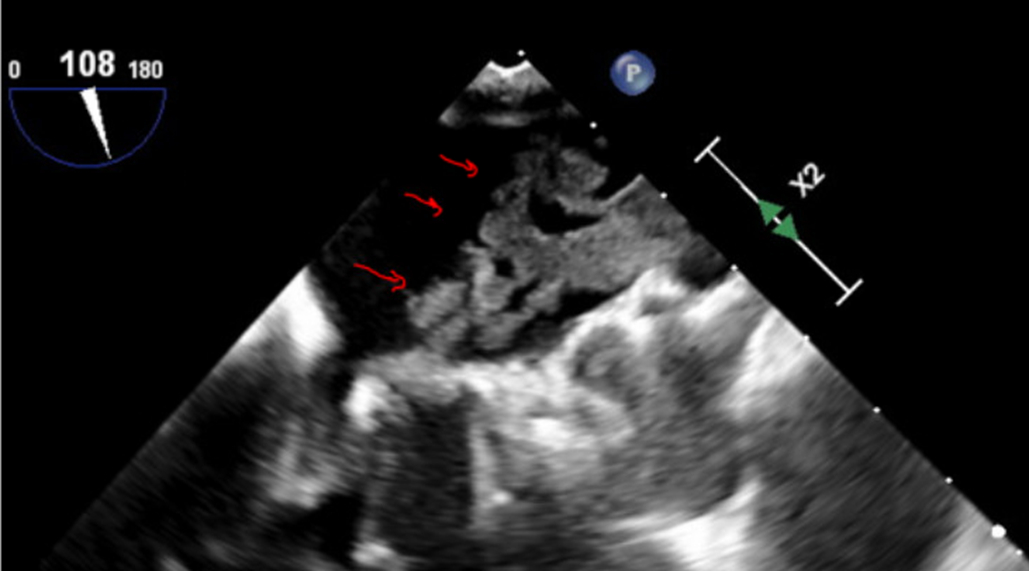

Initial work up